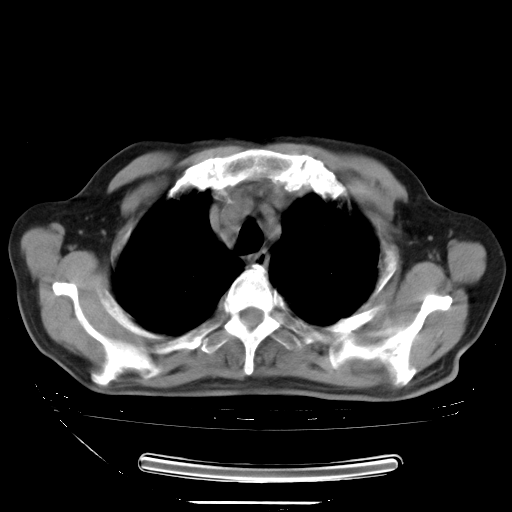

今天复查肺部CT,发现双肺广泛磨玻璃样改变。所以我把3月19日和5月9日相隔50天的肺部CT上传。请大家会诊。

5月9日肺部CT(在4月27日齐鲁医院肺部CT描述部分肺组织磨玻璃样改变,12天后肺组织广泛磨玻璃样改变)

2009年5月9日肺部CT